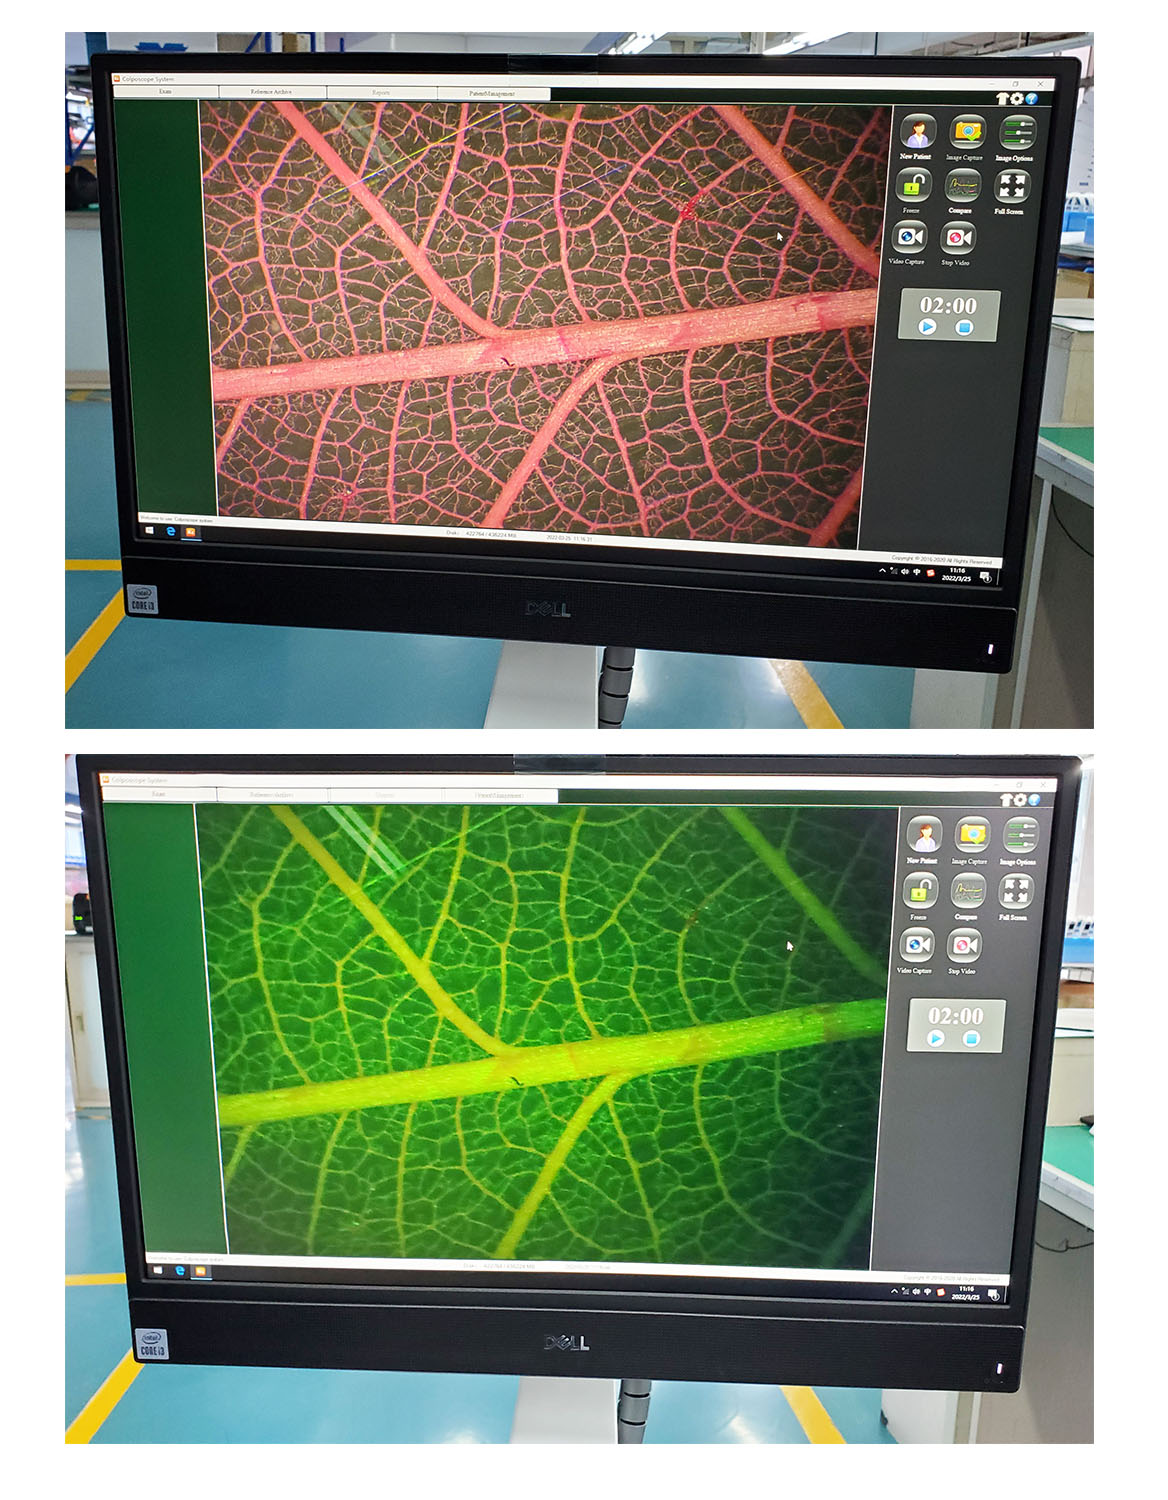

What Sets Kernel KN-2200BII apart from other video colposcope?

**Golden standard of Kernel kn2200 series,with superb German Basler camera 6.37 million effective pixels.

**Combining the advantages of microscope optical system and electronic colposcopy imaging system, it is the perfect combination of optics and electronics.

**Golden standard of this series,with superb German Basler camera 6.37 million effective pixels

**Extra long depth of field, super large field of view, super three-dimensional sense, realistic color reproduction, unique light path design, providing true 3D visual effects for pre-cancerous, pre-lesional punctiform vessels, columnar epithelium and some tiny lesions .

**50times System Magnification ,17 times optical amplication,3 times Digital amplification.able to output divine clear view of the examination lesion parts. Provide doctors with 3D visual image of the epithelial tissues,and different levels of the blood vessels. **LED light source,lifespan more than 20,000hours. **Horizontal Resolution up to 2064.